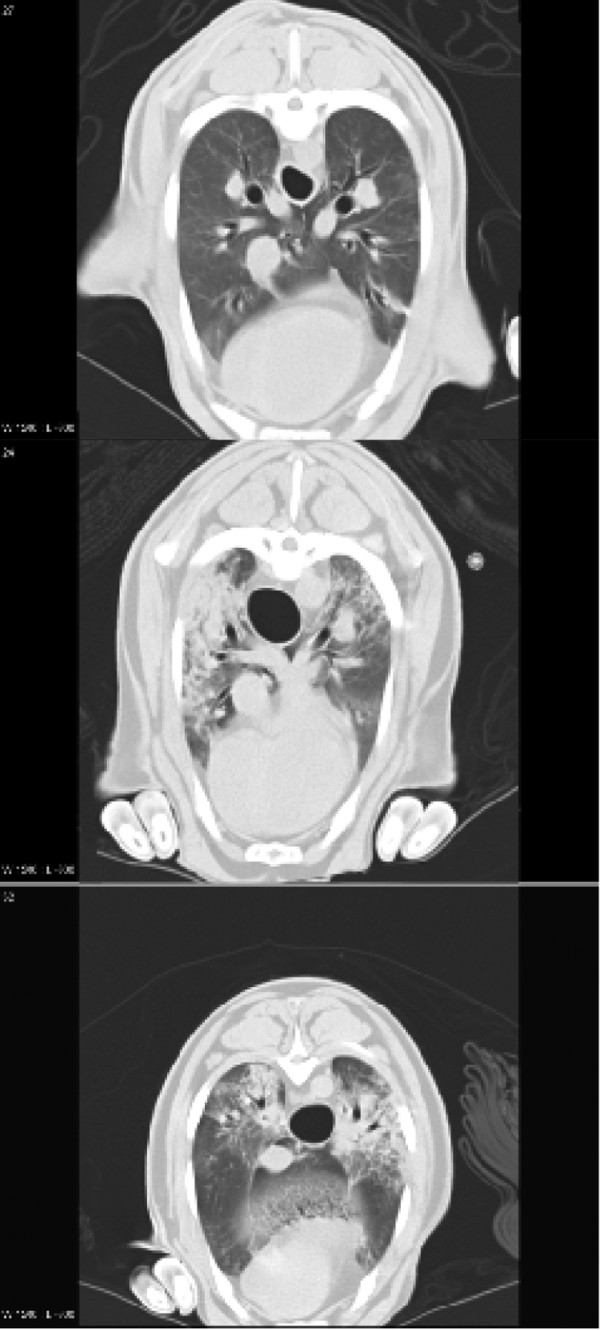

Figure 2 shows representative CT scans taken at FRC of an animal from the sham group (top), one from the LPS (middle) group and one from the LPS+inhAPC (bottom) group. As depicted in Figure 3, at FRC the LPS+inhAPC group presented with a 50% higher volume of well-aerated lung tissue as compared with animals exposed to LPS alone (P = 0.03). However, when examined at end-inspiration, the difference was no longer significant, with an average of 66% well-aerated lung tissue volume in the LPS+inhAPC group compared with 53% with LPS alone (P = 0.06). Correspondingly, when examined at FRC, the gas/tissue ratio was also higher in the LPS+inhAPC group as compared with sheep exposed to LPS alone (Figure 4; P = 0.03), but the intergroup difference was not present at end inspiration (P = 0.09). Total lung gas and tissue volumes (data not presented) displayed no significant intergroup differences at FRC or end inspiration.

Figure 2.

Representative lung computed tomography scans of anaesthetised mechanically ventilated sheep taken at functional residual capacity. Top: sham-operated sheep. Middle: sheep subjected to continuous infusion of lipopolysaccharide (LPS). Bottom: sheep subjected to LPS and treated with aerosolised inhaled recombinant human activated protein C.

The improvement of oxygenation in parallel with the demonstration of larger volumes of well-aerated lung at FRC indicates that inhaled APC may have prevented the emergence of densities occurring with LPS alone (Figures 2 and 3). Such densities are usually seen in patients with ALI [4,19,20]. In support of these observations, investigators recently reported a patient with severe sepsis-induced ARDS who presented with a resolution of the diffuse infiltrates on the chest x-ray in concert with increased PaO2/FiO2 ratio after four days of treatment with inhaled APC [21].